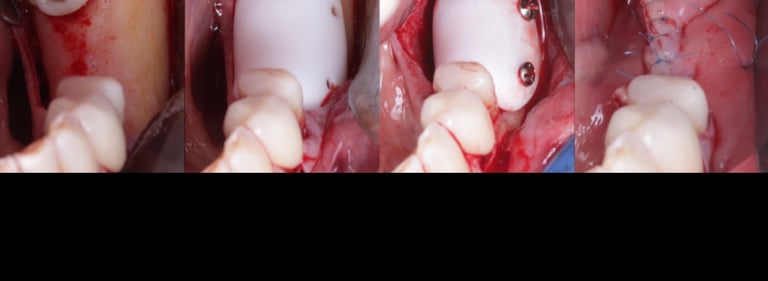

O curso terá como objetivo capacitar o cirurgião dentista quanto à execução dos princípios cirúrgico aplicados às regenerações ósseas guiadas partindo da realização de um perfeito diagnóstico e consequentemente a construção de um planejamento que o levará a um resultado efetivo e dentro das terapias propostas. Serão abordadas as técnicas cirúrgicas mais previsíveis para o aumento ósseo vertical e horizontal utilizando biomateriais analisando a necessidade do envolvimento dessas técnicas com o uso da associação com osso autógeno ou agregados plaquetários. Também serão discutidas as principais técnicas de enxertos ósseos, uso de parafuso Tenda, PRF, PRF block. Dentre outras técnicas.

TÉCNICA DE INCISÃO, RETALHOS, USO PARAFUSO TENDA

REGENERAÇÃO EM ARÉAS POSTERIOR DE MANDÍBULA

TÉCNICA KHOURY MODIFICADA